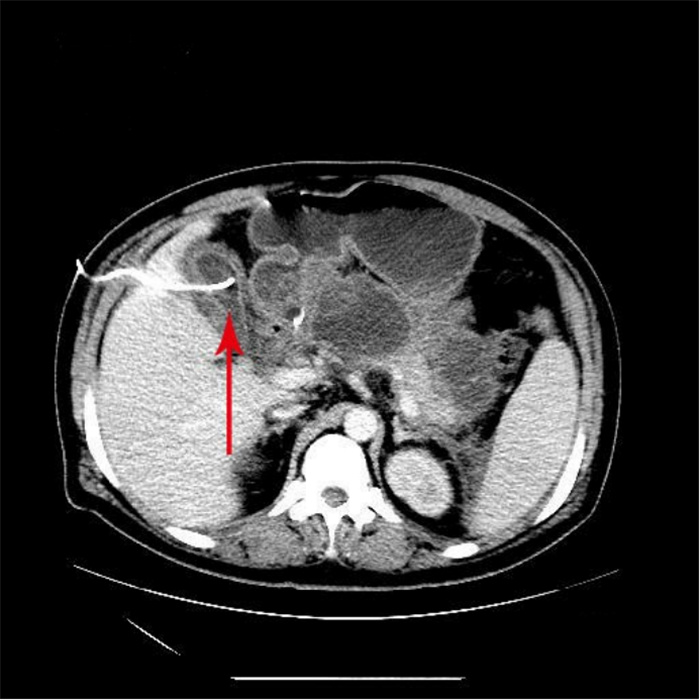

入院第57天,患者再次出现暗红色血便,伴阵发性右上腹痛,无发热、呕血,症状与之前相同。鉴于患者有活动性出血,再次复查胃镜:慢性浅表性胃炎伴糜烂。复查肝功能:γ-GT 844 U/L,TBil 43.6 μmol/L,NCBil 16.6 μmol/L,CBil 27 μmol/L,肝功指标再次回升,γ-GT、CBil明显升高,提示可能出现胆道梗阻。肝胆脾胰腺彩超复查:胆囊肿大、胆囊陈旧性稠厚淤胆(较前无明显变化),胰腺稍大并不均质改变。复查上腹CT:AP复查情况与之前相同,可能有胆囊出血(见图 2)。联合介入放射科行血管造影检查,常规局部麻醉下采用Seldinger技术由右侧股动脉入路,造影发现胆囊动脉分支出血(图 3),超选择胆囊动脉分支用明胶海绵颗粒行栓塞止血(图 4)。同时,行经皮经肝胆囊穿刺置管引流(图 5),病情稳定后带管出院,3月后予以拔除,择期行胆囊切除。

| 胆囊动脉增粗,其分支局部造影剂外溢,未见明显动脉瘤征象 图 3 胆囊动脉造影 |

胆囊动脉出血是罕见的胰腺炎血管并发症,确切的病理基础尚不清楚,推测其出血的机制主要继发于胰管释放的胰酶侵蚀及炎症刺激损伤血管壁[4]。介入放射科的共同参与在复杂胰腺炎的救治中有着重要作用[8],胆囊动脉出血难以被常规的检查发现,尤其是经常规治疗后患者仍有活动性出血时,选择性血管造影应作为首选方法。血管造影仍然是目前判断有无活动性出血的“金标准”,敏感度可达80%~90%以上[9]。血管造影同时发现异常血管、急性出血病因及部位[10],发现病灶的同时可给予介入治疗,有助于迅速维持血流动力学稳定。